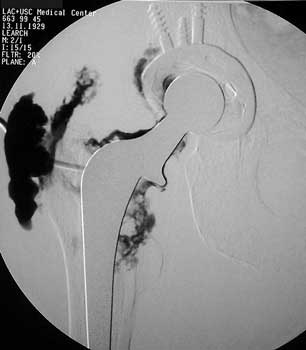

Scar with focal area of drainage. Dry tap secondary to large greater trochanteric bursa with

sinus tract draining to skin

Sinus tract draining posteriorly